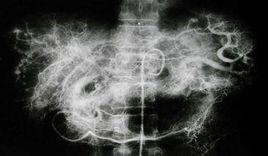

消化系統-肝血池掃描

2.靜脈注射示蹤劑後立即開始動態採集,5s / 幀,採集1~2min;之後每10~15min靜態顯像;一般取仰臥位(前位)、右側位、及後位。

1.動態顯像時,主動脈顯影后,雙腎區顯影,肝內應無放射性濃聚;一般在20s左右,肝內才出現放射性。

2.肝血池相示肝門部放射性略高,其餘部分放射性大致均勻。

3.肝血池相放射性低於脾區及心腔。

4.肝血管瘤在原放射性膠體肝顯像示缺損區內有放射性填充;隨時間漸增強,放射性可接近甚至超過心腔放射性。

5.其他占位病變無填充,或填充不充分,或隨時間漸清除。